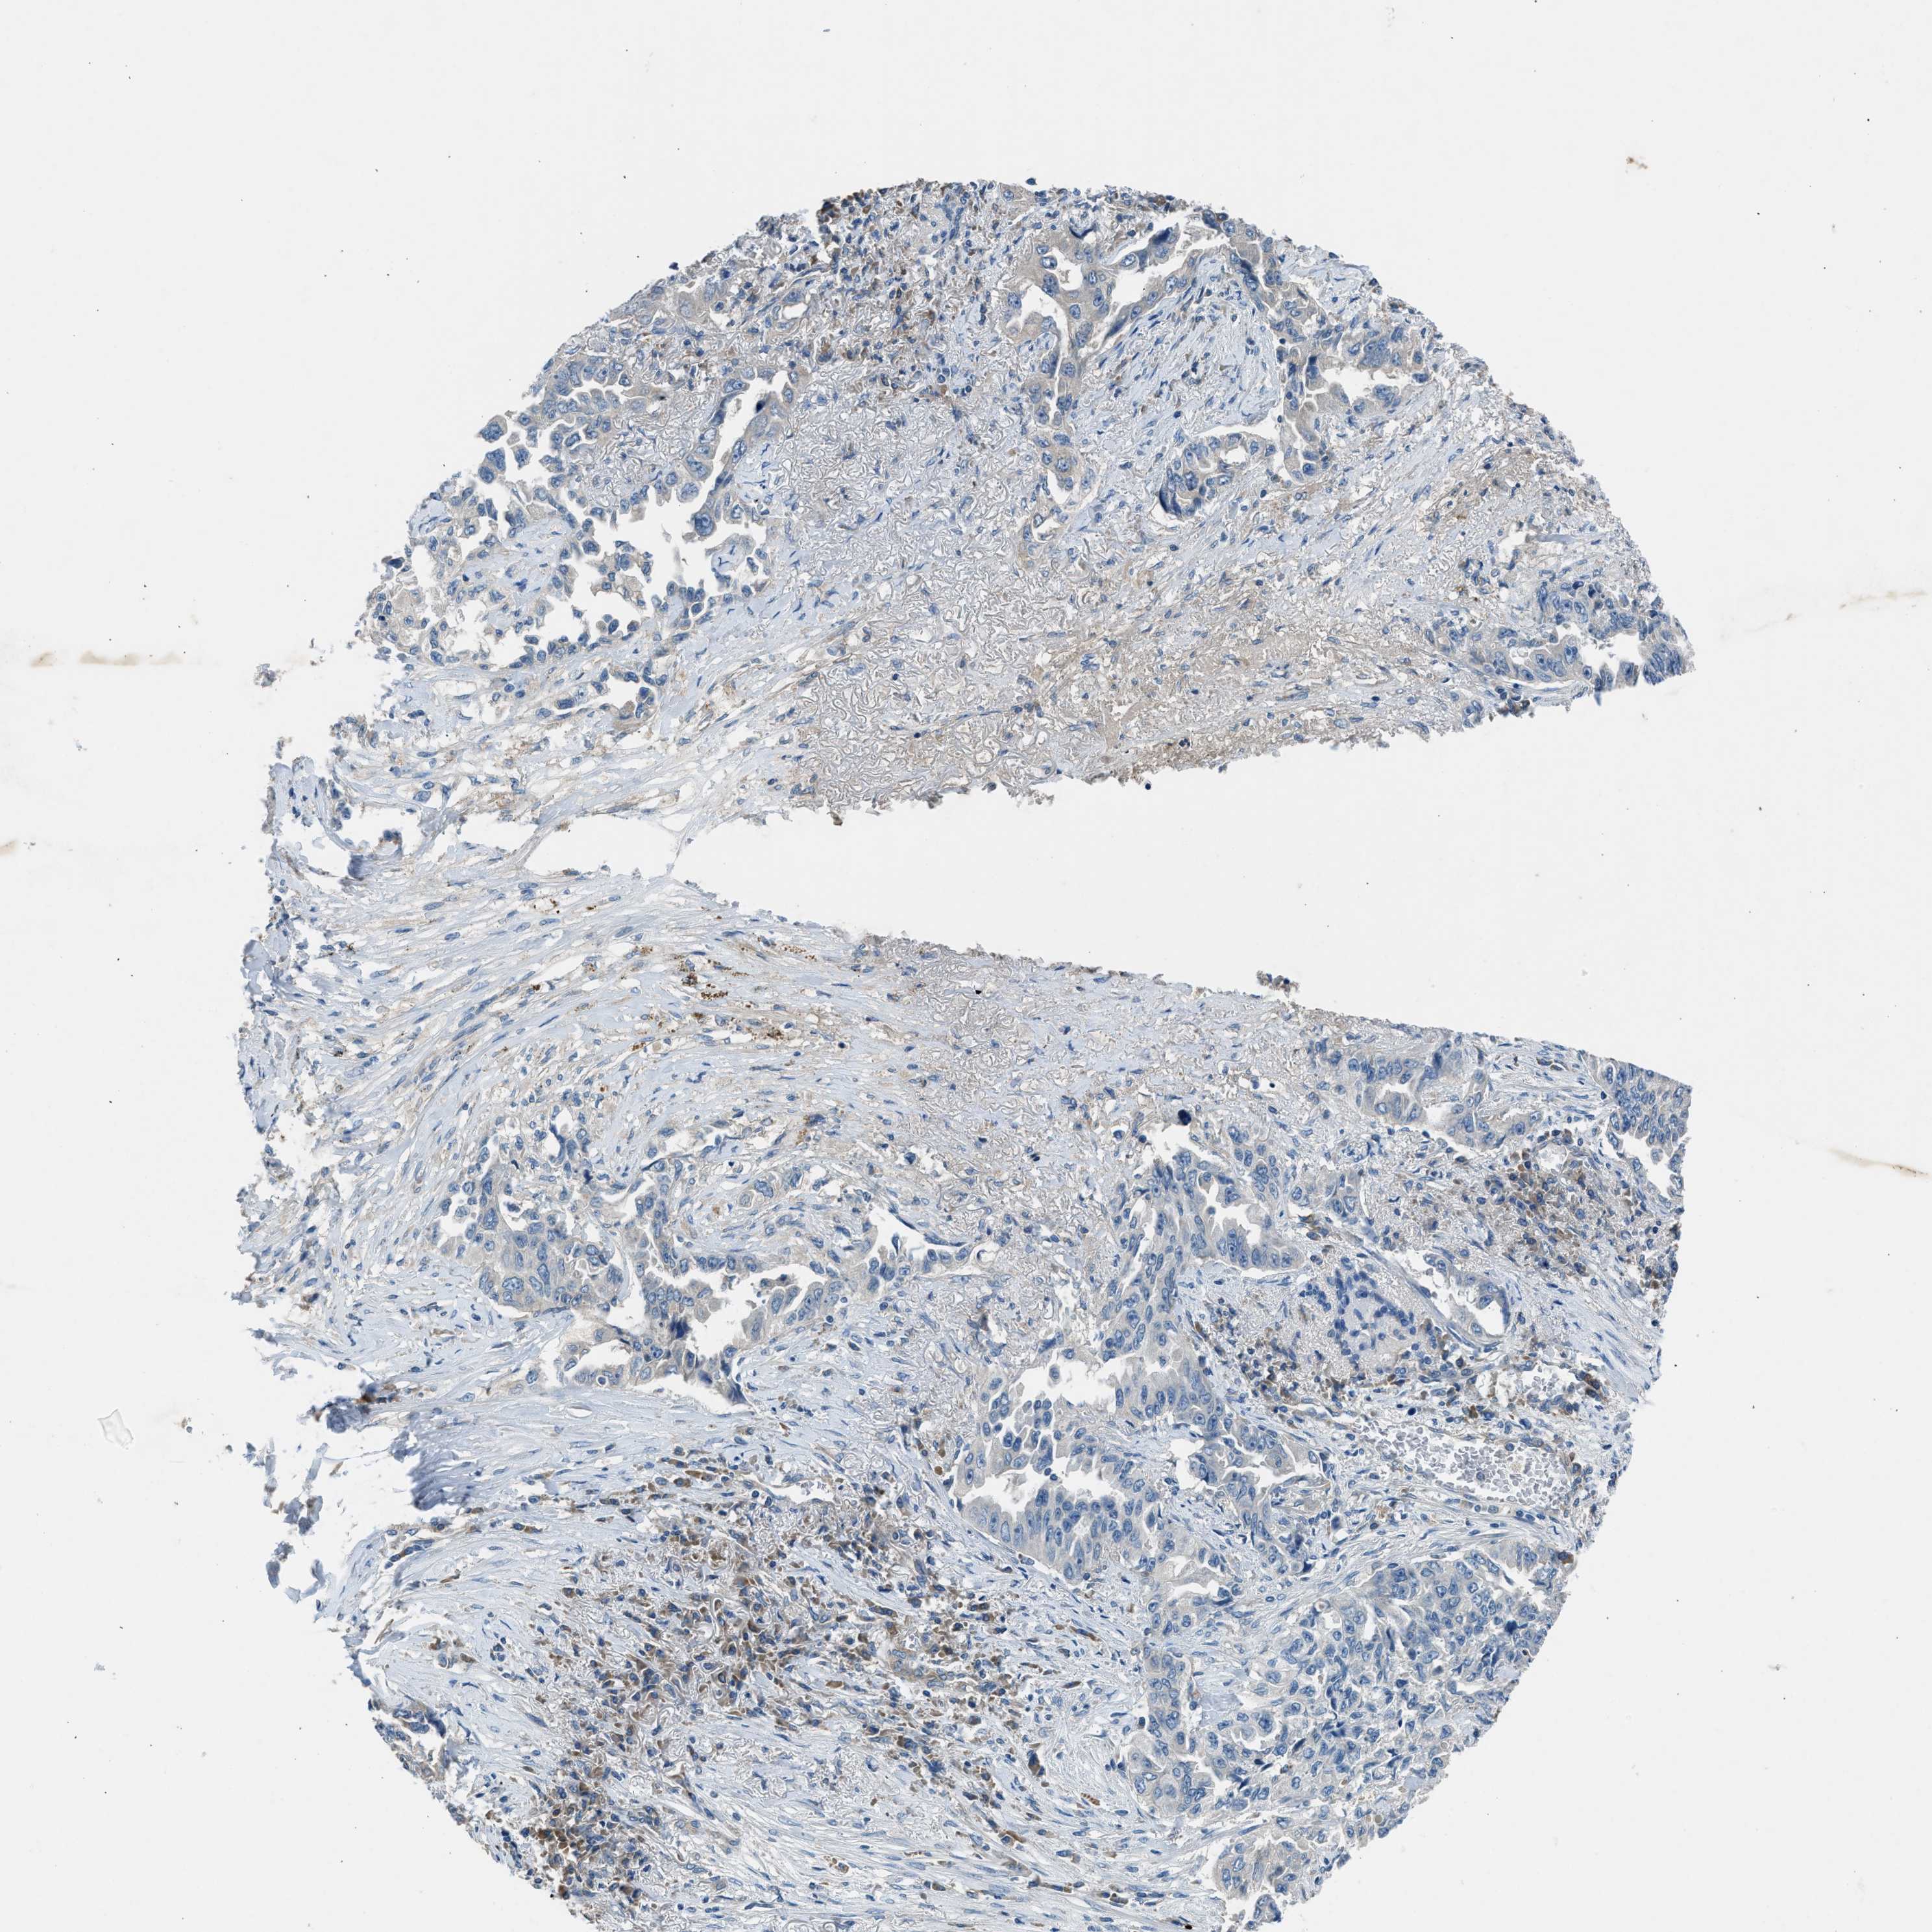

BMP1 is not prognostic in Lung Squamous Cell Carcinoma (TCGA)

Best expression cut offi

: 12.08

Average pTPM 16.9

Number of samples 489